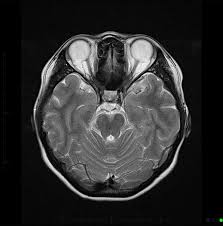

Dementia is a syndrome associated with many neurodegenerative diseases, characterised by a general decline in cognitive abilities and functions that affect a person's ability to perform everyday activities. This typically involves problems with memory, thinking, behavior, and motor control. Dementia ranges in severity from the mildest stage, when it is just beginning to affect a person's functioning, to the most severe stage, when the person must depend completely on others for basic activities of daily living, such as feeding oneself. There are several different forms of dementia, including Alzheimer’s disease, which is the most common.

Signs results when neurons in the brain stop working, lose connections with other brain cells, and die. While everyone loses some neurons as they age, those affected by Dementia experience far greater loss. This is as a result of changing brain regions that trigger the neurons and their connections to stop working. How this initiates, however, is still unknown. The symptoms can vary depending on the type but mainly include: experiencing memory loss or confusion; difficulty speaking, understanding and expressing thougghts; experiencing delusions; taking longer to complete normal daily tasks; and acting impulsively.